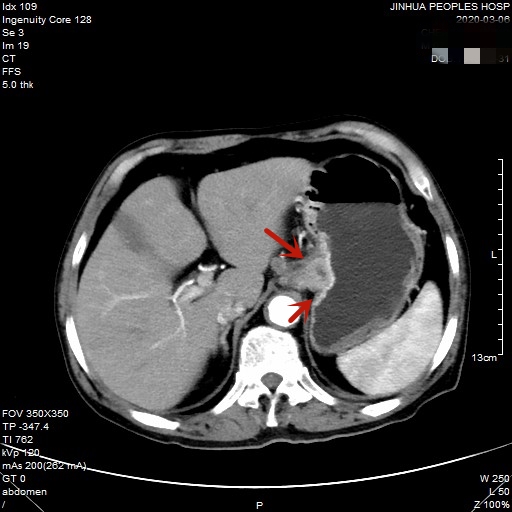

医生予以进一步检查CT增强发现肿瘤倒是没有明显侵犯周围脏器或结构,请我去会诊后,仔细阅片,发现从影像上看还是能够根治性切除的。所以转来胸外科拟进一步行手术治疗。下面是其CT增强的图像:

以上图片红色箭头所指处为贲门部肿瘤